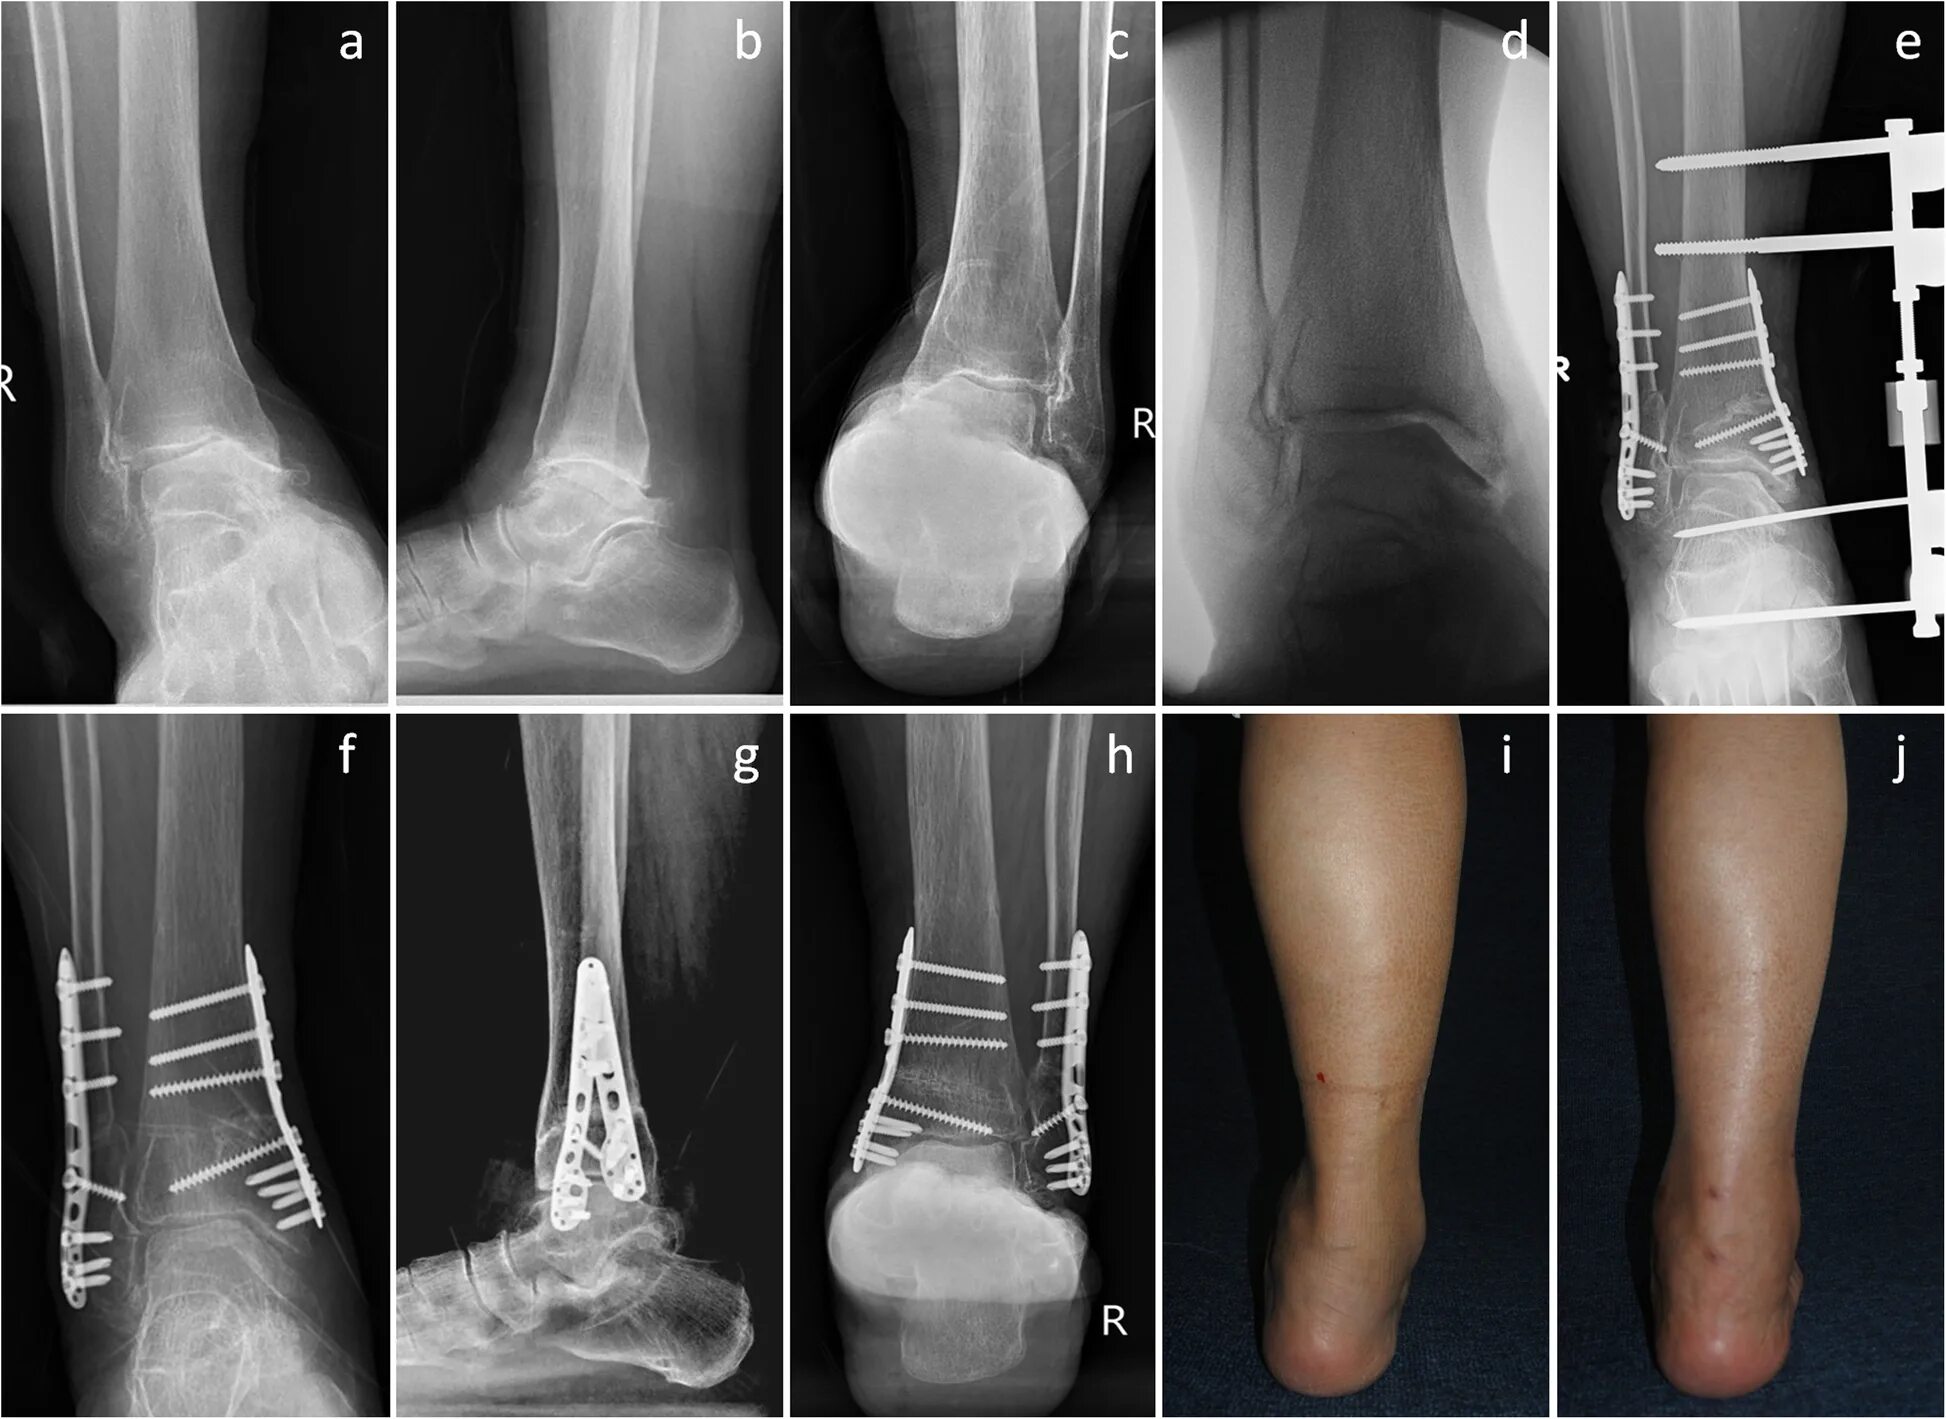

Пяточная остеотомия